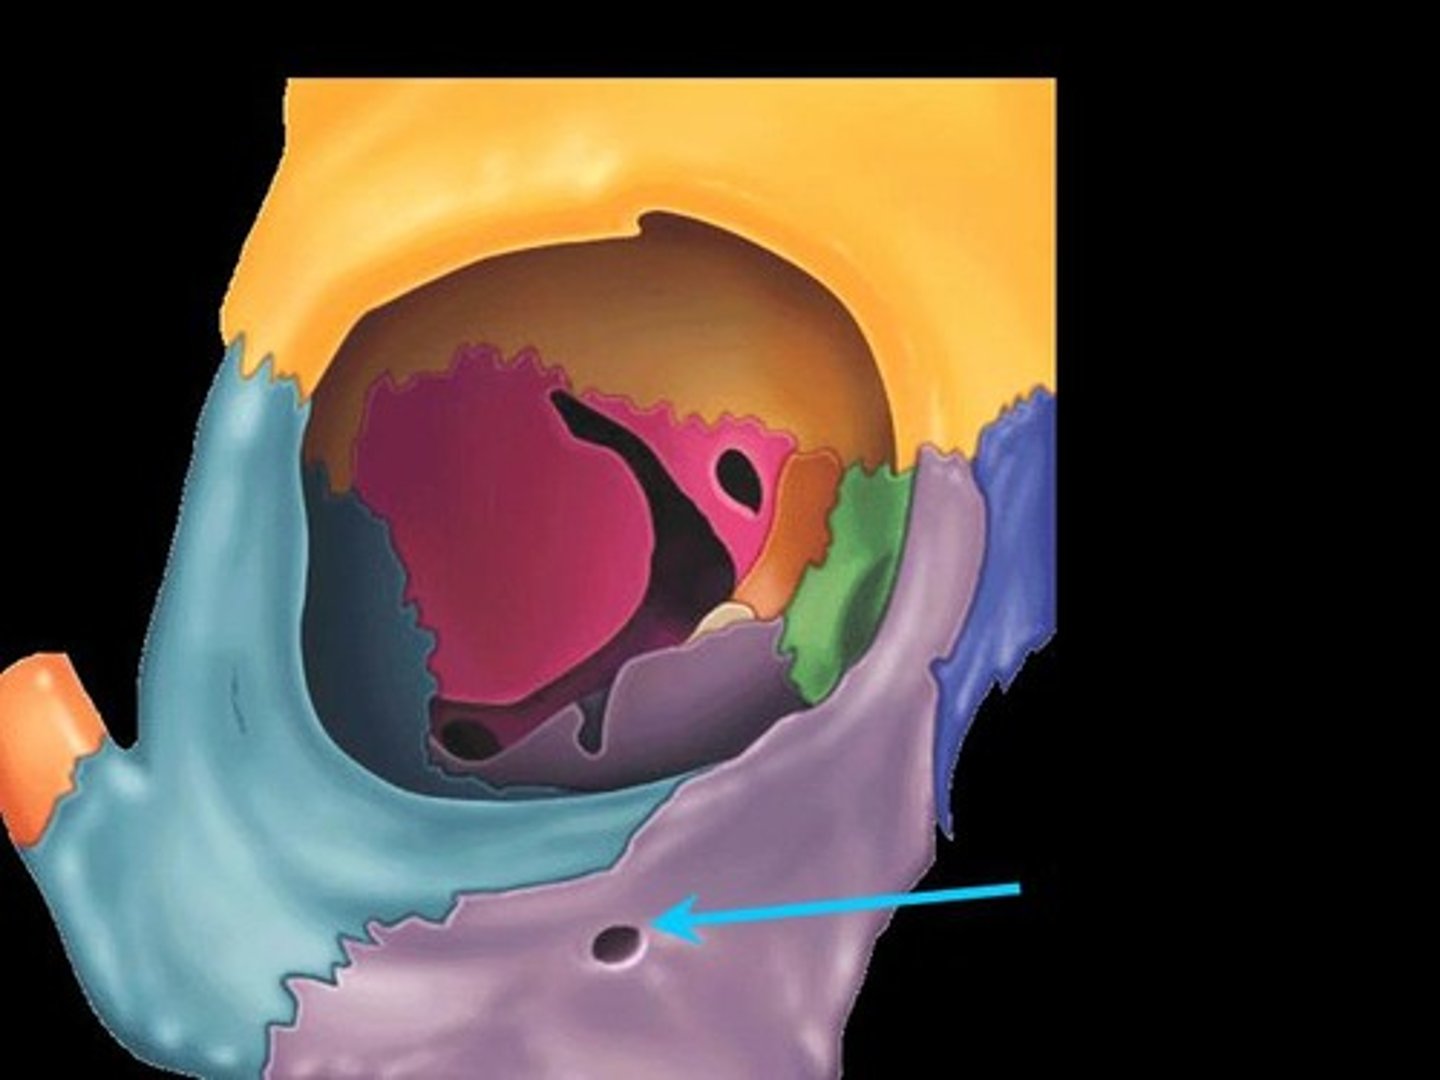

Superior Orbital Fissure

A foramen in the skull lying between the lesser and greater wings of the sphenoid bone

Inferior Orbital Fissure

An opening in the maxillary bone of the skull located below the infraorbital margin of the orbit. It transmits the infraorbital artery and vein, and the infraorbital nerve, a branch of the maxillary nerve.

Optic Canal

A cylindrical canal running obliquely through the lesser wing of sphenoid bone near the base where it joins the body of sphenoid. It transmits the optic nerve and ophthalmic artery.

Foramen Rotundum

Located at the base of the greater wing of the sphenoid, inferior to the superior orbital fissure. It provides a connection between the middle cranial fossa and the pterygopalatine fossa. The maxillary nerve (branch of the trigeminal nerve, CN V) passes through this foramen.

Foramen Spinosum

The middle meningeal artery, middle meningeal vein, and the meningeal branch of the mandibular nerve pass through the foramen.

Foramen Ovale

An oval shaped opening in the middle cranial fossa located at the posterior base of the greater wing of the sphenoid bone. It transmits the mandibular division of the trigeminal nerve (CN V3) and the accessory meningeal artery.

Lacrimal Bones

Small, thin bones located at the front inner wall of the orbits (eye sockets)